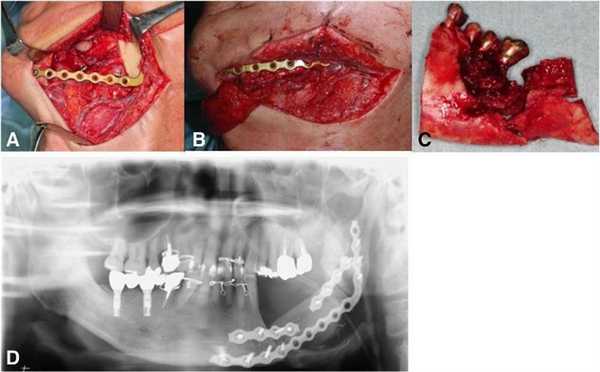

На первом этапе лечения пациент прошел курс 30 сеансов гипербарической кислородной терапии, что позволило лишь незначительно улучшить имеющиеся симптомы поражения. Учитывая, что на рентгенологических снимках не было замечено никакого прогрессирования области деструкции, была проведения частичная резекция области нижней челюсти с последующим восстановлением дефектного участка посредством свободного микроваскулярного лоскута из малоберцовой кости. Фиксация трансплантата проводилась с использованием титановой пластины (фото 4).

Фото 4: а) Сегментированная резекция пораженного участка нижней челюсти; b) локализированный костный трансплантат из области малоберцовой кости; c) резецированная нижняя челюсть; d) ортопантомограмма после операции.